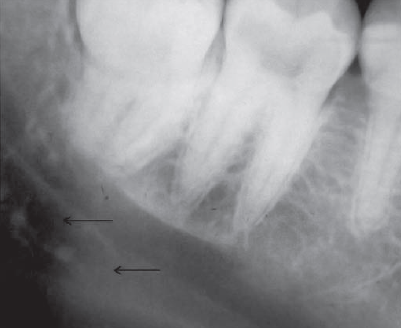

60. What is showing by arrow?

Submandibular Gland Fossa a bone depression on the lingual surface of the mandibular body, immediately below the mylohyoid ridge in the molar area. often appears as a radiolucent area with the sparse trabecular pattern